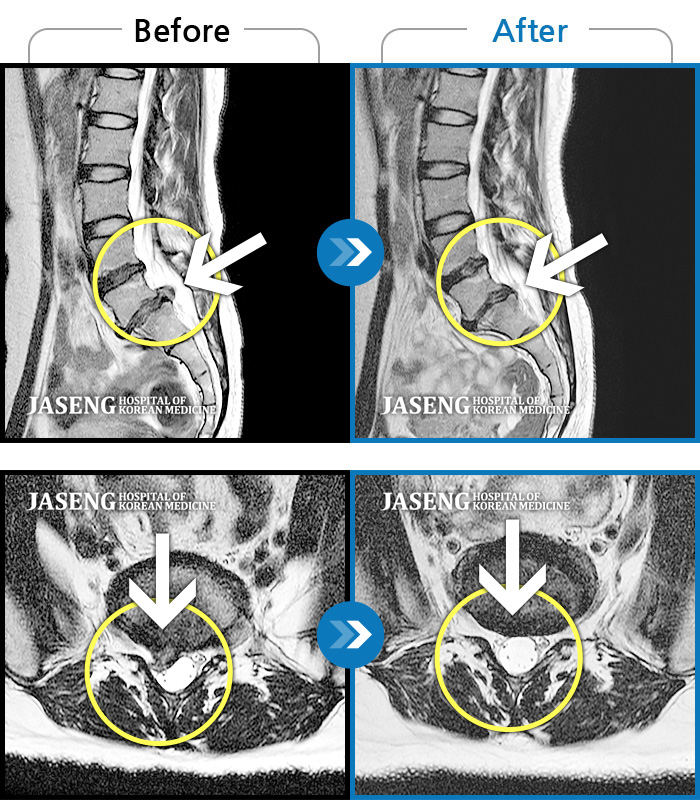

• 허리디스크